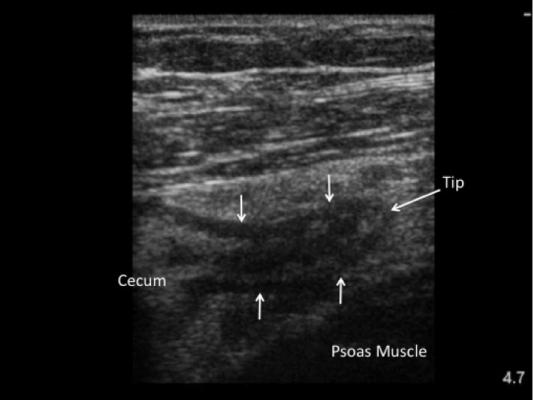

February 28, 2014 — Using portable ultrasound as a first-line imaging study in kids with suspected appendicitis helps reduce emergency room length of stay and reduces the need for CT scans, according to a team of Mount Sinai researchers. Point-of-care ultrasonography has a specificity of about 94 percent. Results from the study were published online Feb. 10 in the peer-reviewed journal Academic Emergency Medicine.

The study showed that emergency department length of stay declined by 2 hrs and 14 minutes (46 percent decrease) for those requiring radiology department ultrasound and nearly 6 hours (68 percent decrease) for those requiring CT scan when point-of-care ultrasound was inconclusive as a first-line imaging study. No cases of appendicitis were missed with the point-of-care ultrasound protocol and no unnecessary surgeries were performed for a normal appendix. With focused ultrasound training, pediatric emergency clinicians were able to evaluate ultrasound exams with the similar accuracy as radiologists (about 94 percent accuracy).